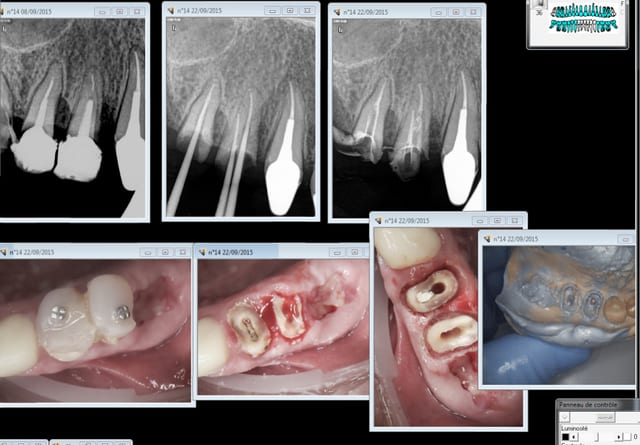

Peu de temps après, il fait une exposition pulpaire sur une 26 présentant une carie pourtant à peine dentinaire. L'exposition baigne dans la salive, la digue n'est pas posée, contrairement aux consignes du service. "Gentil", j'explique que l'exposition était évitable et constitue un mauvais facteur pour le pronostic de la dent, d'autant plus au vu de la contamination salivaire. Faciès bovin, aucune réaction. J'explique en d'autres termes : "Tu vois cette petite fille de 7 ans ? Tu comprends que sa 26 est probablement perdue au long terme par ton acte ?". Aucune réaction. J'insiste et lui demande sincèrement : "Ça ne te fait rien ? Tu ne te sens pas un peu triste ?". Il répond nonchalamment : "J'sais pas, faut qu'j'aille chercher une digue, c'est ça ?".

Je reçois une petite de 8 ans avec cellulite sur 46 : dent perdue, à avulser. Je consulte ce dossier et découvre qu'elle avait été pourtant vue par cet étudiant il y a plusieurs mois pour "abcès 46". Patiente jamais recontactée. Je l'appelle : il me répond "j'ai pas eu le temps de faire l'endo, je pensai la rappeler en septembre".

Au bout d'une année de ce comportement, j'émets un avis lors des délibérations. Il s’avère alors que cet avis est le même dans d'autres disciplines. Les quotas/notes sont à la limite de la moyenne. Après discussion, une décision collégiale est prise : les quotas/notes ne sont pas "remontés" et l'étudiant redouble.

Il vient se plaindre : "Vous m'avez fait redoubler pour une pulpo !". Je ne doute pas qu'il dira à ses amis "J'ai redoublé parce que TiGabi il m'aimait pas !". Et dans 10 ans, il écrira sur Eugenol : "Les profs à la fac, c'est rien que des salauds !".

De deux, tu penses que ton iconographie m'impressionne? Il n'y a rien de très compliqué.

Je suis vraiment content que tu me dises ça. Cette iconographie me demande énormément de temps sur des enfants de 4-6 ans et dans le flux d'un cabinet libéral. Comme ce n'est "pas compliqué" et que tu as plein de conseils pour les enseignants, tu va pouvoir m'aider à préparer les cours ?